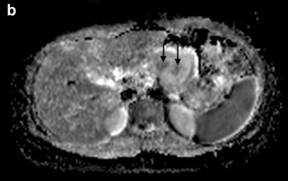

DW-MRI (Figure 4a) was performed (using b values of 50, 400 and 800) and the mean apparent diffusion coefficient (ADC) map was calculated (Figure 4b). The lesion presented a relatively high ADC value (1.8 x10-3 mm2/sec) compared to the ADC of the normal pancreatic gland (1.4 x10-3 mm2/sec), although there were some intralesional small areas of relatively low signal (minimum values of 1.3 x10-3 mm2/sec). T2/DW fusion imaging was performed (Figure 4c). Gadolinium-enhanced MR imaging (Figure 5) showed early peripheral enhancement of the fibrous pseudocapsule. No central contrast enhancement was observed.

Figure 4. a. Axial diffusion-weighted image (b value of 800 sec/mm2) shows a lesion with low signal intensity with some small central areas of higher signal intensity from restricted diffusion. b. Apparent diffusion coefficient mean value of the lesion is 1.8x10-3 mm2/sec with the central hypointense areas having a minimum value of 1.3x10-3 mm2/sec (arrows). c. T2-weighted and diffusion-weighted imaging were fused displaying a colored map of abnormal diffusion parameters. |